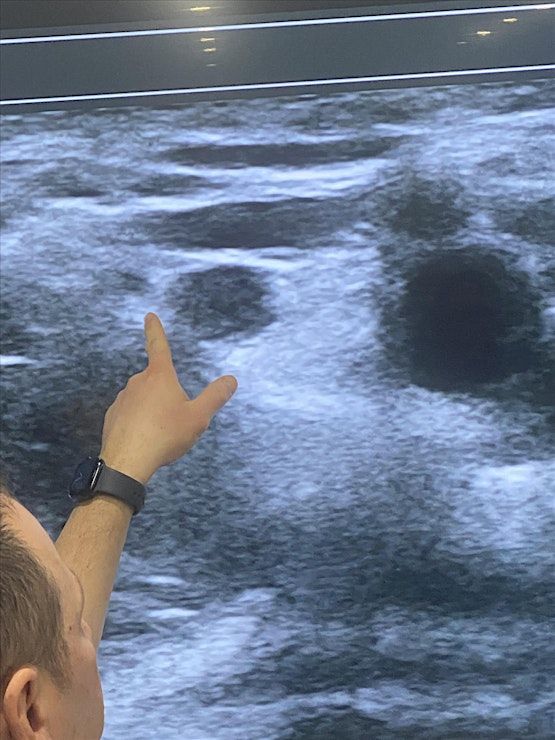

This 1 day intensive workshop has been developed for both novices and advanced pain physicians providers who would like to either learn the basics or further advance their skills in ultrasound guided pain procedures and regional anesthesia. Participants will have up to 6 hours of hands on ultrasound scanning on live models and lecture to learn and identify different sono‐anatomy. At the end of the workshop, you will be expected to have gained thorough knowledge and immense confidence in the use of ultrasound for pain procedures

• Identify normal sono‐anatomy and aberrations

• Increase the ability to detect critical structures and improve patient safety while performing pain procedures

• Perform nerve block | epidural and large joint imaging with ultrasound

13:00 -15:00 Hands on Scanning: Live Models

Scanning Live Models for Ultrasound Guided Joint Injections & Nerve Blocks